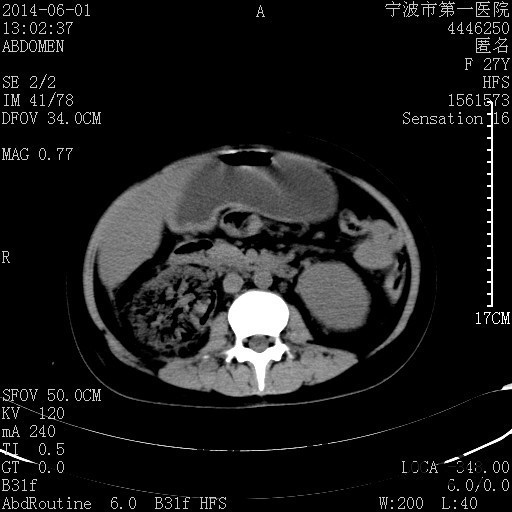

患者,女,27岁,因“右下腹疼痛伴呕吐2天”入院 患者无明显诱因出现右下腹疼痛伴呕吐、发热,体温最高39度,急诊CT示:右肾集气,考虑气性肾盂肾炎。

查体: 右肾区叩击痛,右下腹压痛,无反跳痛。 辅助检查: 空腹血糖9.7mmo/L,餐后血糖18mmol/L 血常规:白细胞 11.3*109/L, 中性百分比 77.4%, 血红蛋白 8g/L, 血小板 319*109/L 尿常规 WBC+++ 生化:白蛋白 37.5g/L,肝肾功能正常 泌尿系CT:右肾集气

诊断为“气性肾盂肾炎,感染性休克,糖尿病酮症酸中毒” 血、尿、脓液培养均示“克雷伯杆菌” 入院第2天行“右双J管置入术” 入院第3天、7天行“右肾穿刺造瘘术” 入院1月行“右肾切除术” 术后顺利康复出院。